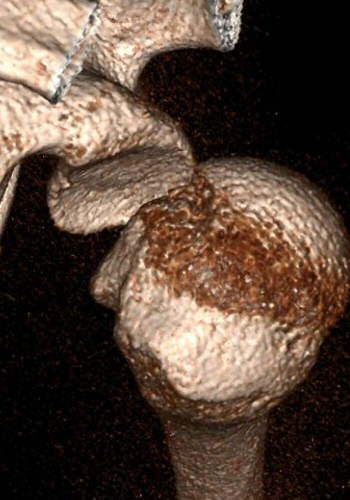

Bakre luxation, patienten hade mycket ont, kunde inte röra axeln alls. På frontalbilden ligger kaput roterat, på sidobild ligger kaput inte rätt i leden, på 3D-rekonstruktion syns felställningen tydligt (delar av nyckelben och akromion bortredigerade).